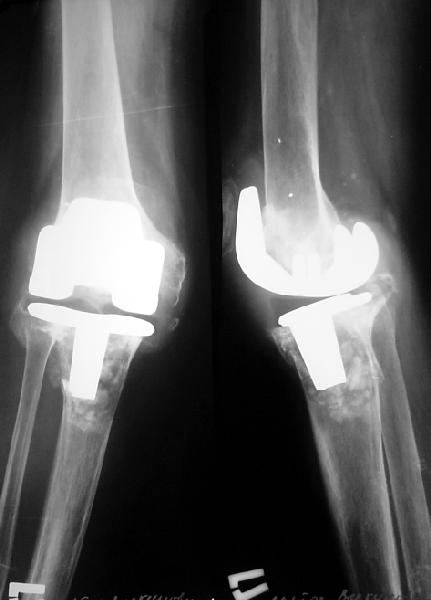

Пациентке 1954 г.р. по поводу ревматоидного поражения коленных суставов в 1995 г. выполнено эндопротезирование правого коленного сустава (Biomet AGC); в 1996 г. - компрессионный артродез левого коленного сустава, анкилоз достигнут. В апреле 2003 г. больная упала, получила перелом на уровне проксимальных метафизов обеих костей правой голени. Имеется клиническая и рентгенологическая картина нестабильности бедренного и большеберцового компонентов эндопротеза. При пункции получено 60 мл серозно-геморрагического отделяемого, посев роста микрофлоры не выявил. Получает глюкокортикоиды per os 5 мг в сут., диклофенак 100 мг/сут.Что можно в данном случае предпринять? Если ревизию, то какую модель протеза лучше испльзовать? Замыкания второго коленного сустава хотелось бы избежать.

Наверное, ревизионное протезирование. Если боковые связки в порядке, то любую ревизионную модель, хоть того же Biomet.

Если имеется выраженная боковая нестабильность, то, наверное, единственный вариант - Sulzer GSB.

Если толщина кошелька этой дамы позволяет или у Вас хорошая социальная программа, предложил бы ревизионное э\протезирование Nex Gen LPS со стержневой б/б надставкой S/A. Но надо ли торопиться, пока достаточно свежа травма?